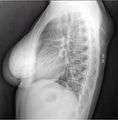

X-ray of the lipoma.

X-ray showing lipoma